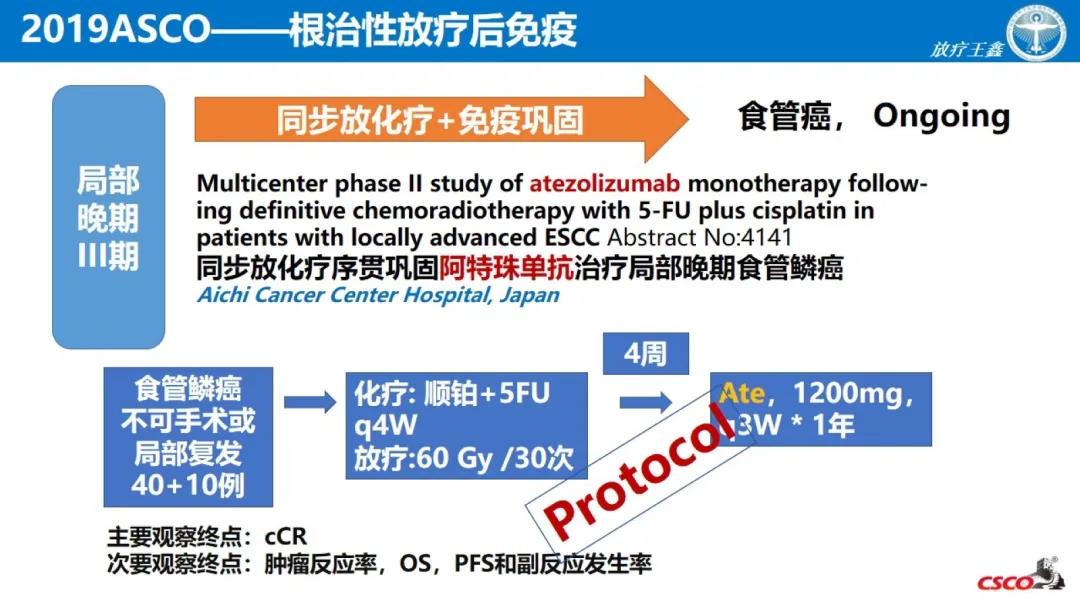

食管癌在中国和全世界都是高发的恶性肿瘤之一,传统治疗手段对食管癌的总体疗效不尽如人意。近年来,放疗与免疫治疗在局部晚期和晚期食管癌中不断取得突破。在2020 CS...